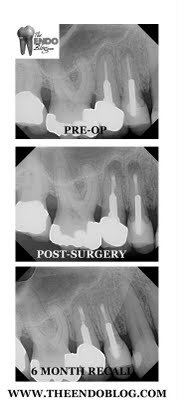

The following case is a similar, double apicoectomy. The CBCT confirmed that there were no missed canals. The large posts and good crown margins were the reasons we chose surgery over non-surgical retreatment.